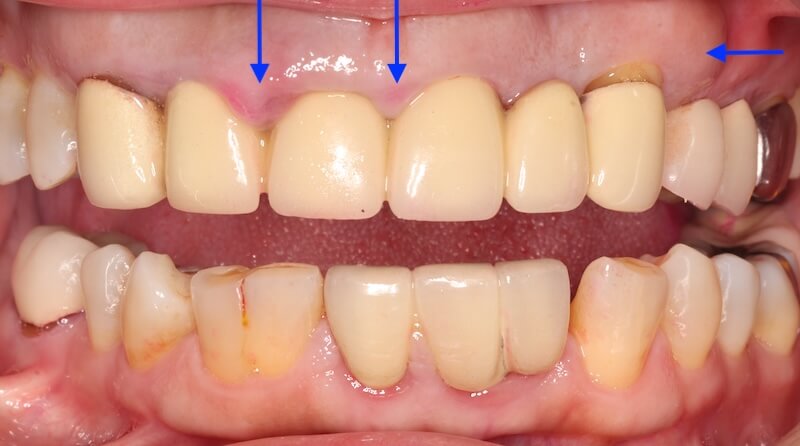

口內的檢查可以看到,在上顎前面六顆假牙,牙齦明顯腫起來。這可能來自兩個原因:

另外一個原因就是假牙邊緣比較深入牙齦深處,侵犯到牙齒的生物寬度,也會產生類似這樣的表徵。

經過全口初步檢查以及X光片的檢查,我的診斷是全口中度慢性牙周病。治療牙周病過程中我會搭配顯微鏡和水雷射,也就是『顯微水雷射牙周病治療』。不過在牙周治療前,我們也要先把上述的兩個會加重牙周病的問題一併考量,治療才會有效果。

拆除舊假牙換上臨時假牙之後,開始進入牙周病的療程。我們會先將治療前口內狀況完整記錄,詳細分析每一顆牙齒的牙周狀況。

經過第一階段的療程後,我們持續追蹤 Ms.H 刷牙的情況,並且在大約兩個月後追蹤整體復原的進度,我們可以看到牙齦腫大的狀況明顯改善了許多,消腫以後產生了不少縫隙: